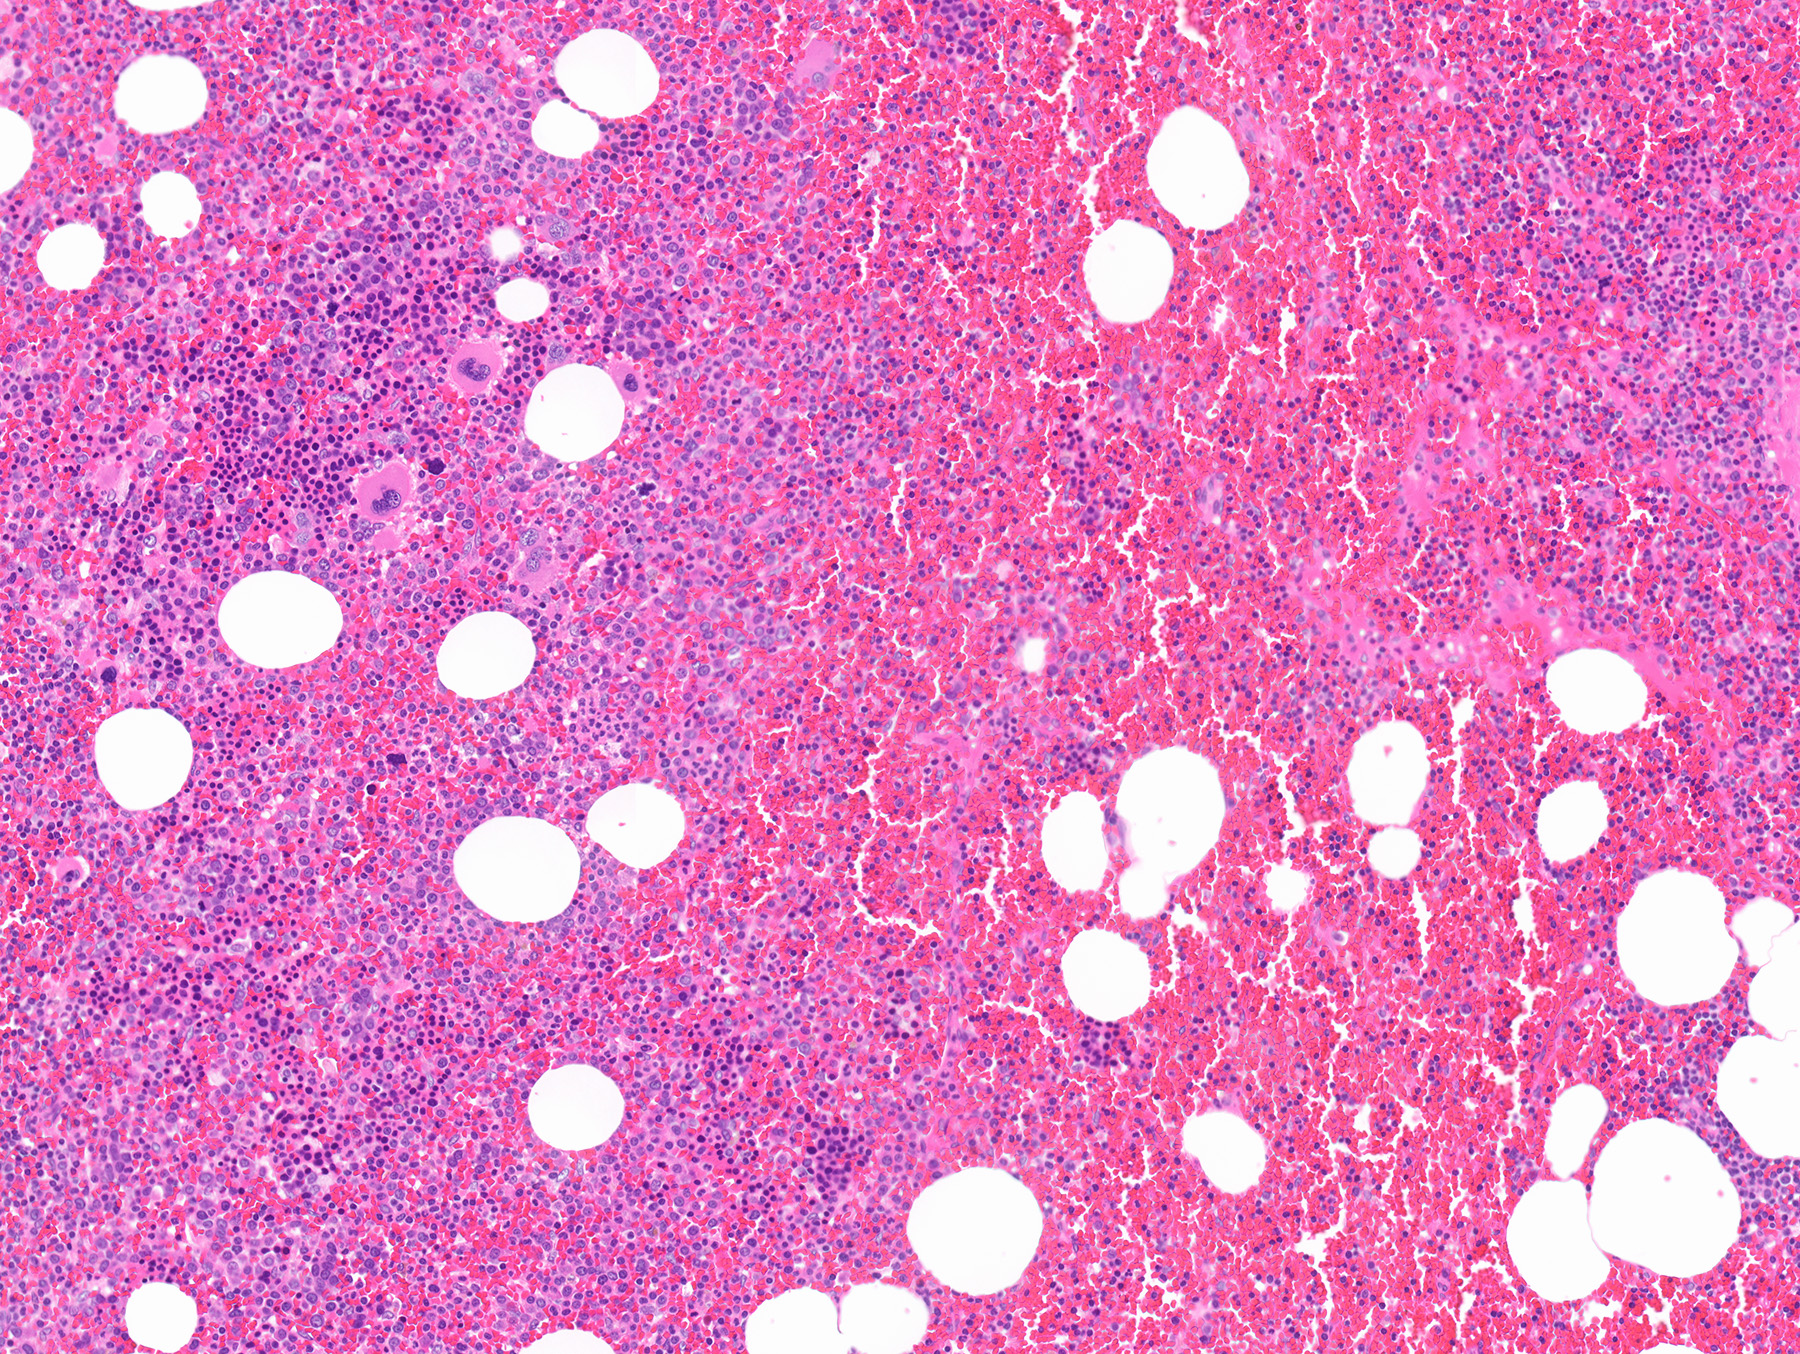

- Mixture of mature adipocytes and extramedullary trilineage hematopoietic cells with full maturation (similar to a hypercellular bone marrow) but often with a markedly increased number of megakaryocytes (Am J Surg Pathol 2006;30:838)

Microscopic (histologic) images

Contributed by Debra L. Zynger, M.D., Anil Parwani, M.D., Ph.D., O. Hans Iwenofu, M.D., Ph.D. and @ThatGlassTho on Twitter